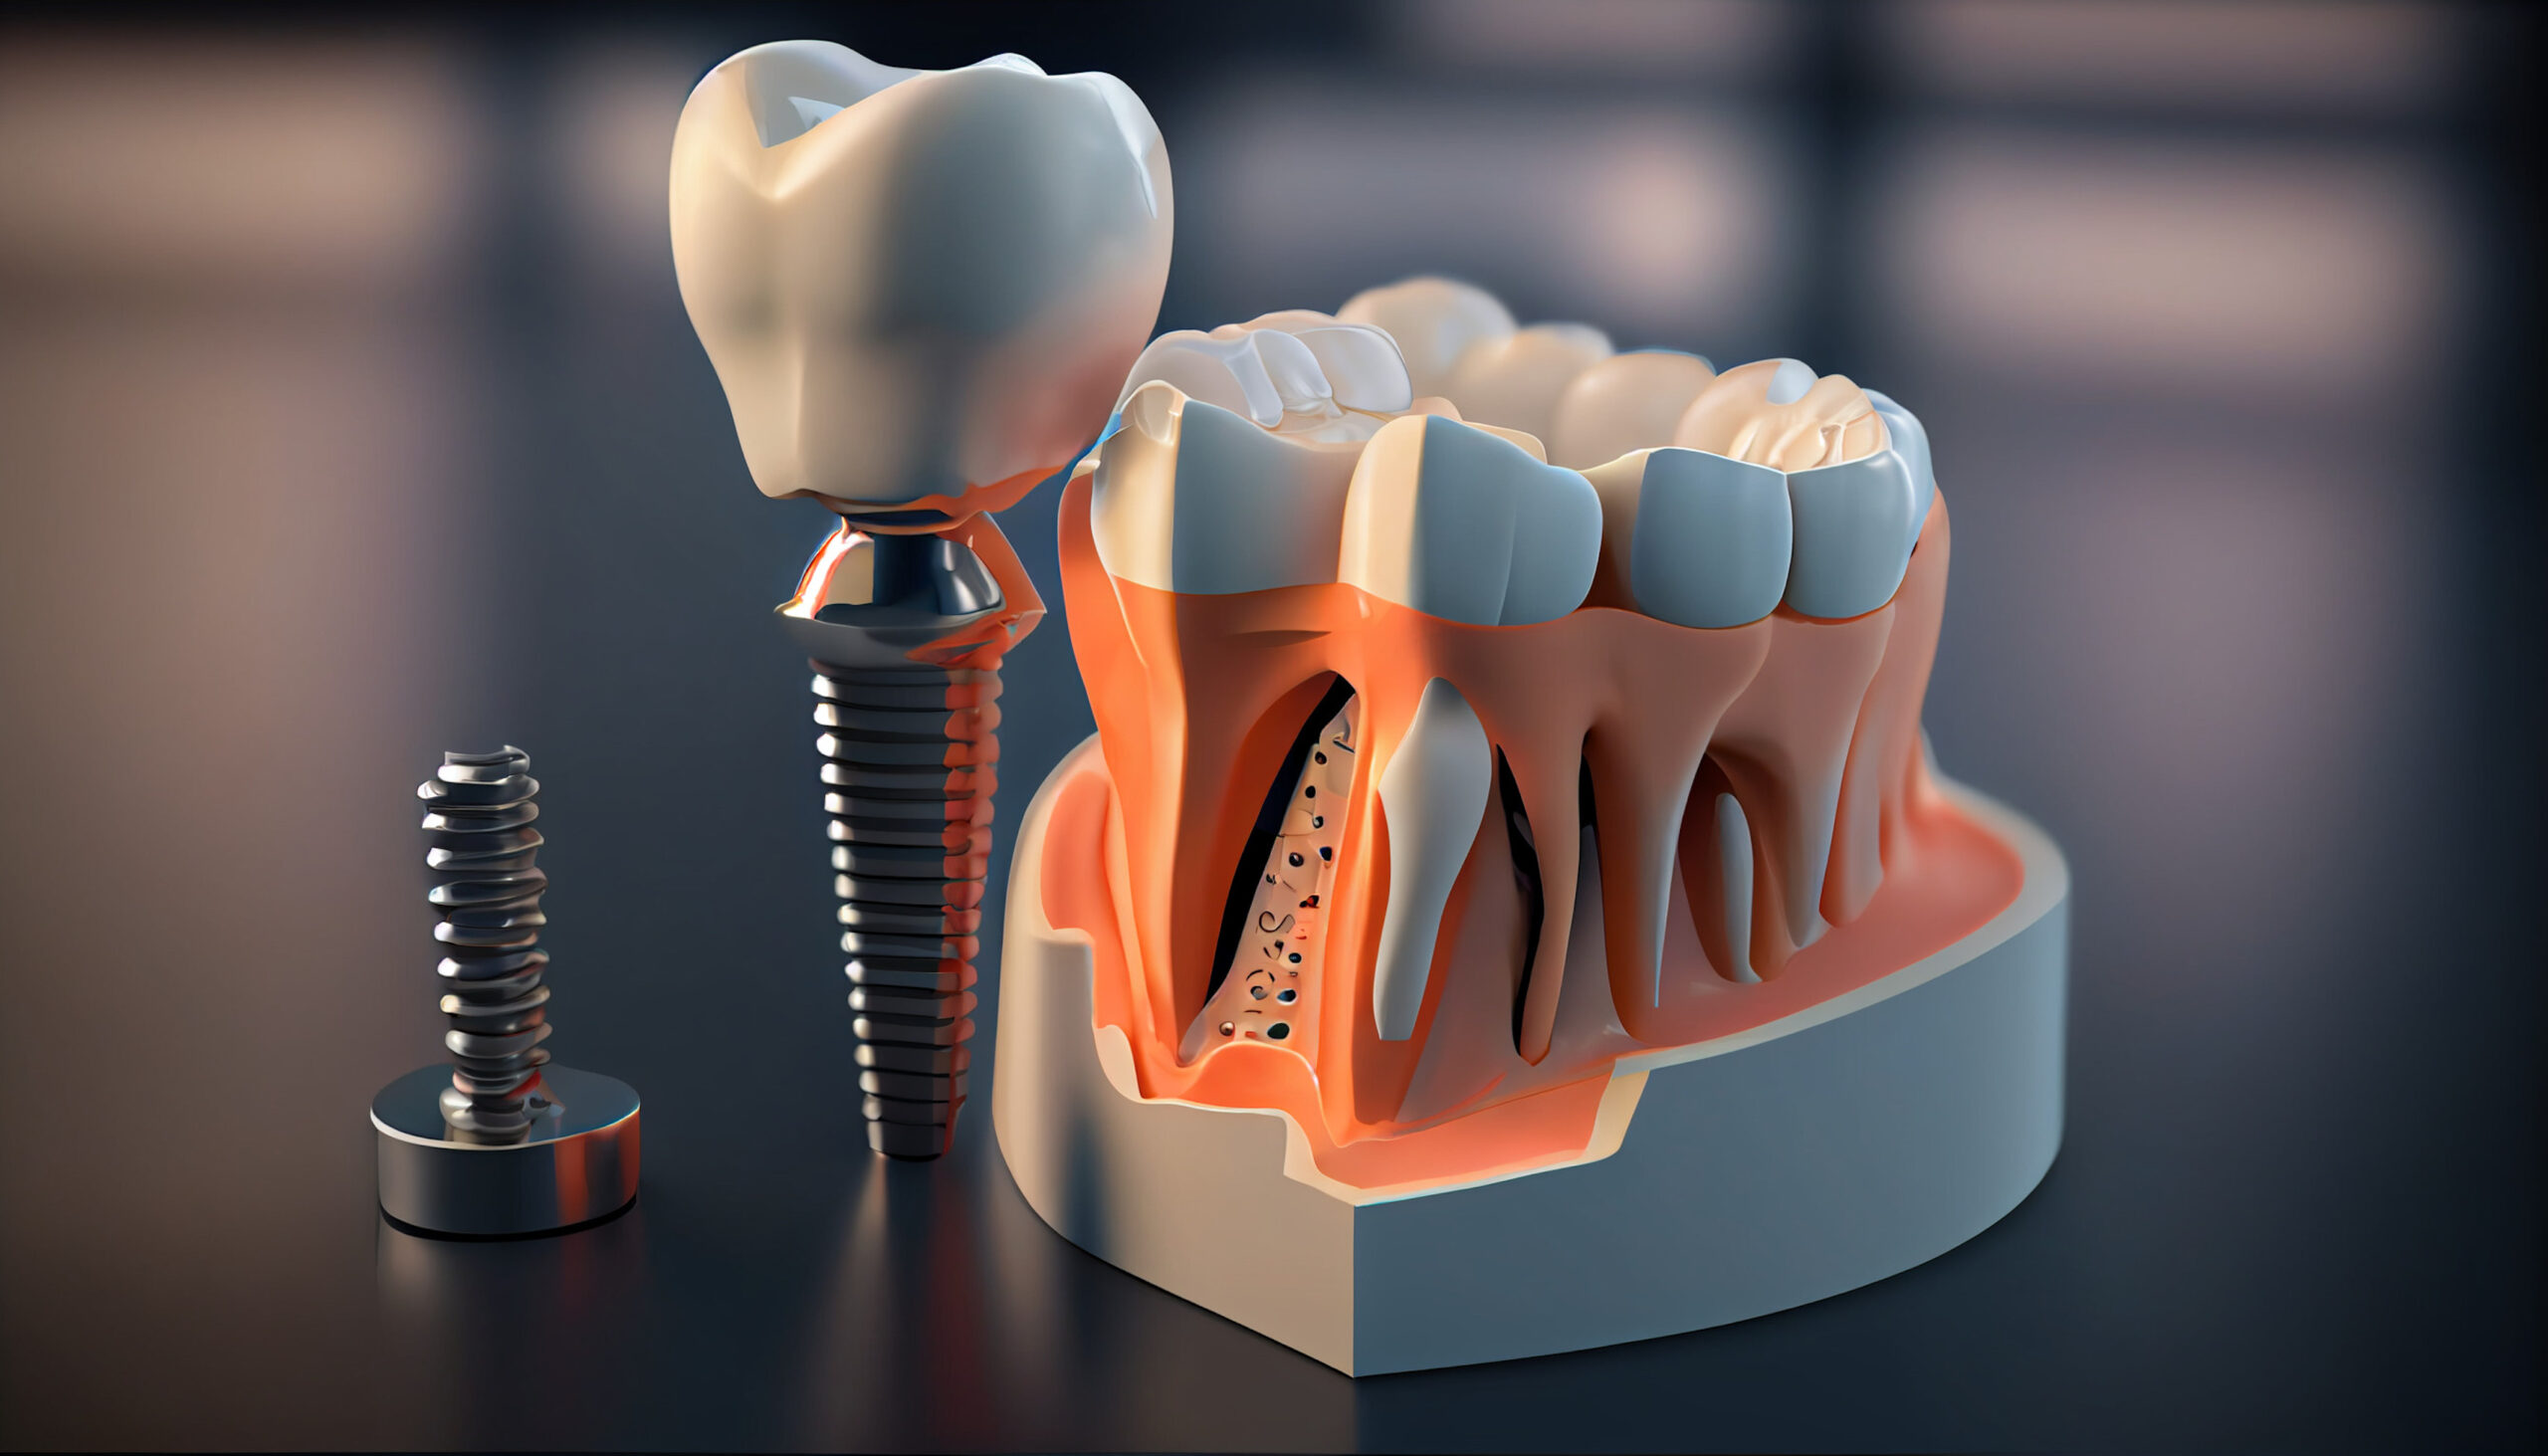

インプラント治療は、失った歯を補う治療法の一つです。顎の骨にインプラント体を埋め込み、人工歯を装着することで噛む機能を回復させます。

インプラントは、顎の骨を支えとして利用するため周囲の歯を削る必要がなく、ご自身の歯と変わらない噛み心地を保てることが特徴です。ご自身の歯のように独立しているため審美性が高く、精巧に作られた人工歯は天然歯に見劣りしません。

ただし、インプラントは外科手術が必要な治療です。治療期間は6か月〜1年程度と長期間に渡ります。また、保険適用外の自由診療になるため、治療費が高額です。